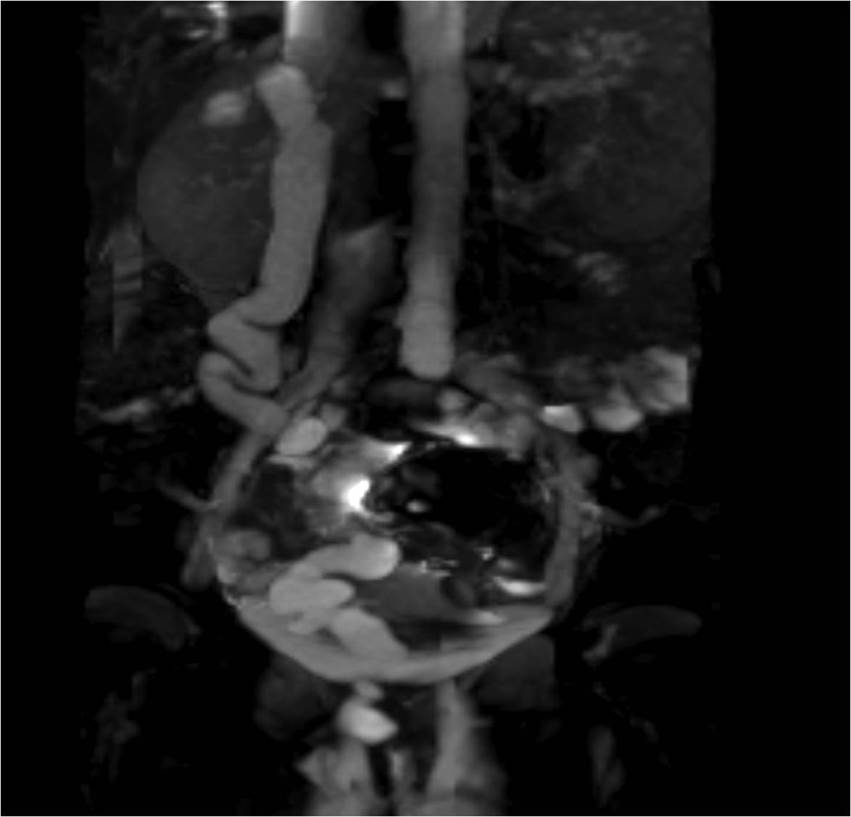

We aimed to present a rare case with right ectopic ureter (EU) occurred in different clivage and right double ureteropelvic system (DUS) which causes diurnal urinary incontinence (DUI) and serious social problem in a young girl accepted late period. A 14-years-old girl was evaluated for ectopic ureter causing urinary incontinence and recurrent infection. She had periodic pains in right lomber region and congenital urinary incontinence which repeated 5 minutes after toilet need. Her internal clothes were frequently wet. Hydroxyzine HCl, imipramin HCL, Sertralin HCL, desmopressin, and oxybutinin HCL had been used for the patient who applied to different health institutions. She did not have any benefits of these drugs. She had right ectopic ureter, associated with urethra and double collecting system in right kidney after performing renal USG, cystoscopy, VCUG, urodinamy, MRU, and MAG-3. Right ectopic ureter was found, dissected, and cut at the limit of urethra. Ureteroneocystostomy was performed. Vesicoureteral reflux was not identified in control VCUG. Postoperative evaluation documented no urinary incontinence and no low life quality. The patient has urinary continence, high life quality, and normal kidney function and she has no social problem. Ectopic ureter should be considered in the differential diagnosis of children and adolescents which applied with the congenital diurnal incontinence considering bladder dysfunctions treated with medical and conservative approaches.